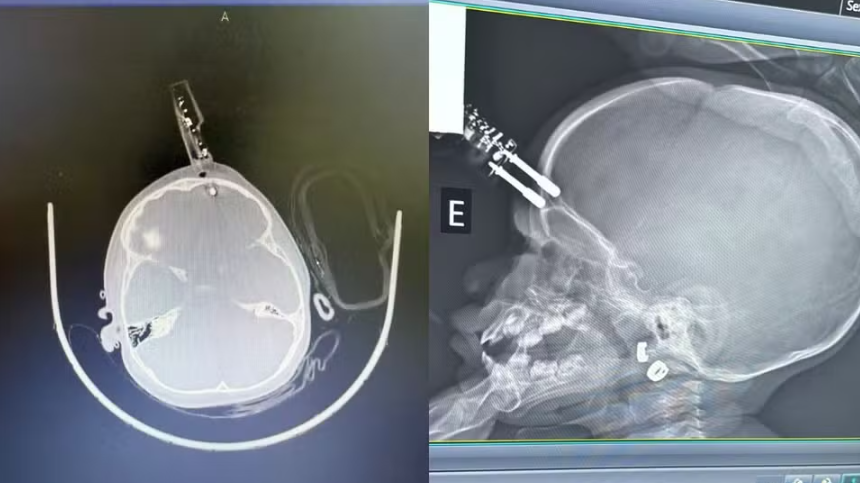

A menina passou por cirurgia de emergência no Complexo de Saúde São João de Deus, onde o objeto foi retirado e a área, reconstruída. O atendimento rápido evitou hemorragia e infecção, incluindo o risco de meningite.

A principal hipótese é que a criança segurava o carregador no momento da queda. O objeto perfurou a região frontal da cabeça, perto do olho. “Se tivesse atingido o olho, poderia causar perda da visão”, explicou o médico.